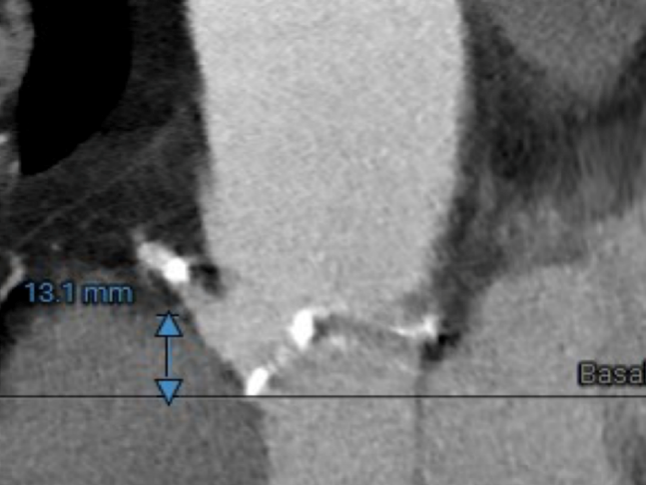

冠脉高度测量

LEFT CORONARY

左冠开口高度14.0mm

RIGHT CORONARY

右冠开口高度13.1mm